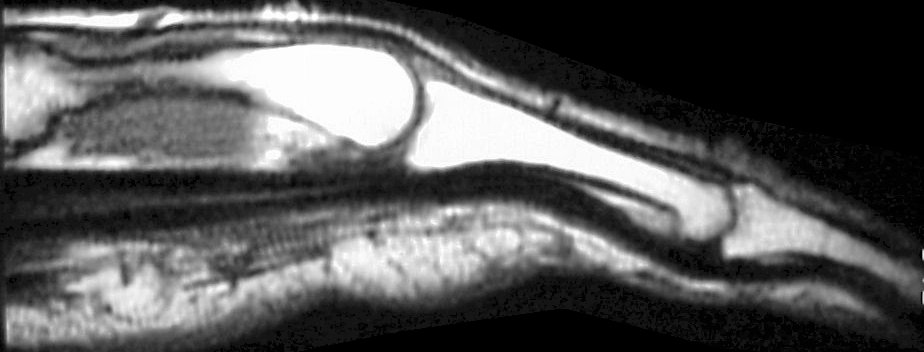

The diagnosis was flexor tendon rupture, site uncertain. He was explored and found to have ruptured both flexors of the small finger within the carpal tunnel:

Thorough exploration of the hook of the hamate and pisotriquetral joint were remarkable only for what appeared to be loss of soft tissue cover of the radial cortex of the hook of the hamate. No fracture line was identified, but because of this abnormality, the hook of the hamate was removed. The small profundus was reconstructed with an end to side weave to the ring finger profundus tendon: